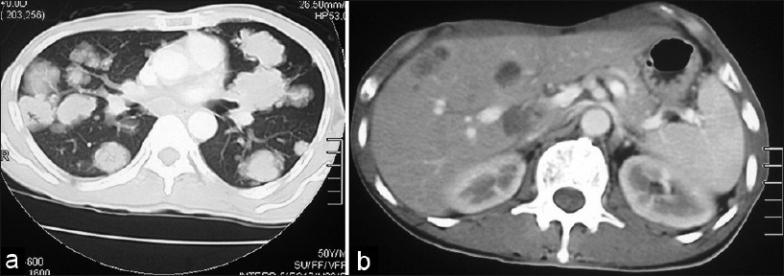

Subcutaneous metastasis from carcinoma larynx is a rare presentation and to the phalynx is the rarest. We herein describe a case report of carcinoma supraglottic larynx, which is involving all five distal phalanges of left hand with simultaneous metastases to lung and liver. Acrometastasis is an unusual presentation, which might mimic an infectious or inflammatory pathology. The brief report highlights the importance of clinical awareness of metastatic dissemination to unusual sites in the face of increasing cancer survivorship.